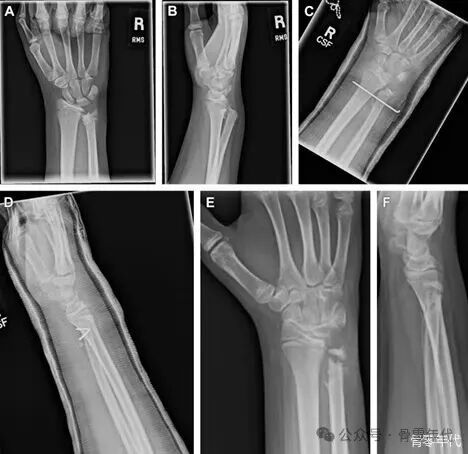

(A) 青枝骨折,(B) buckle骨折,(C) 完全未移位骨折,(D) 完全移位骨折。